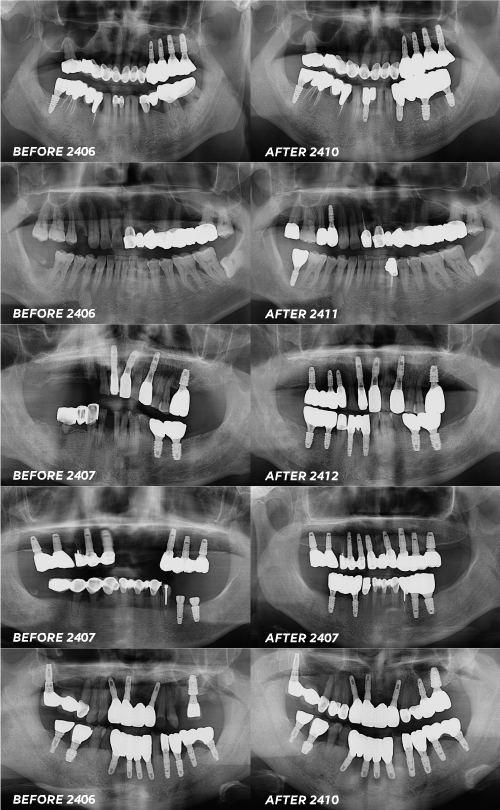

앞니 임플란트 후기 왜 찾아봐야하나요? 앞니 임플란트의 경우에 후기를 꼭 찾아봐야 하는 이유는 웃을때 또는 말할때 등 보여지는 치아이기 때문입니다. 물론 당연히 어금니도 중요하고 기능적인 부분도 봐야하는 부분이지만 특히나 앞니의 경우 기능과 미관 두가지를 다 저울질 해봐야 하는 부분이라고 볼 수 있습니다. 앞니임플란트...

그렇기에 더욱 꼼꼼한 앞니임플란트 후기 탐색이 필요한데요.